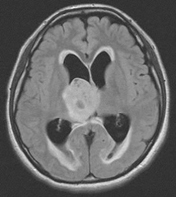

下図のCT画像のように、クモ膜下出血では頭蓋底のクモ膜下腔に白い出血が広がり、頭部CTで確実に診断できます。クモ膜下出血と診断されれば、直ちに脳MRAや脳血管撮影で脳動脈瘤の部位を特定し、開頭クリッピング手術やカテーテルによるコイル塞栓術(血管内手術)が必要です。